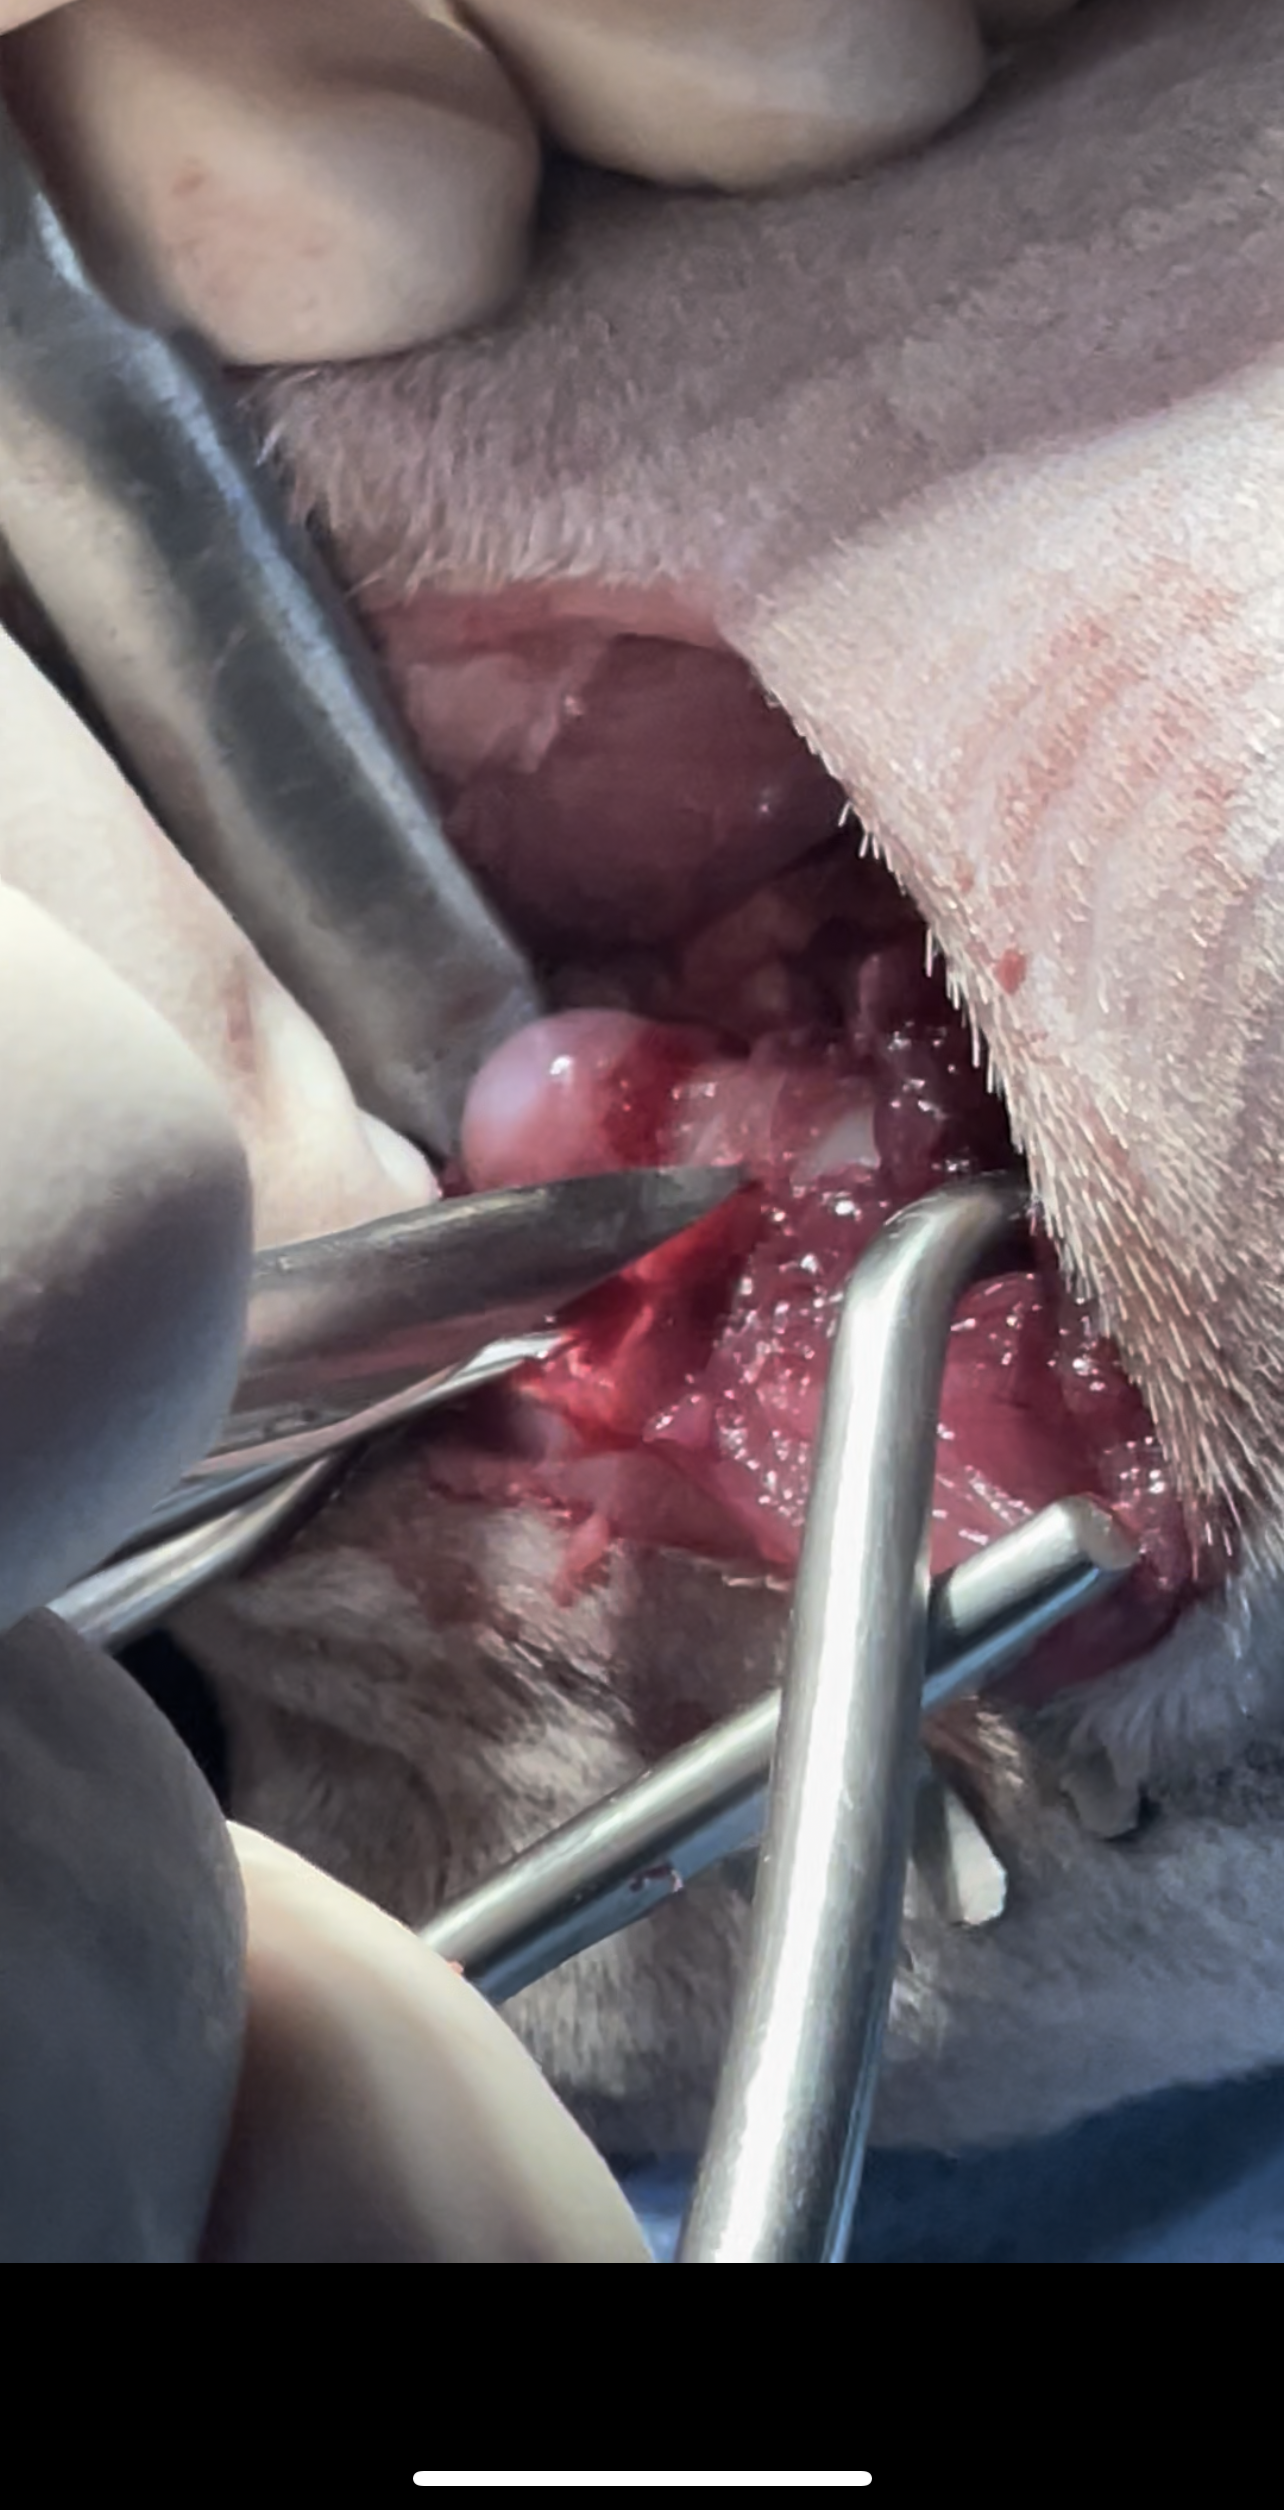

Bilateral FHO was recommended starting with the right most affected limb and the other to be scheduled after 2 months

Surgery